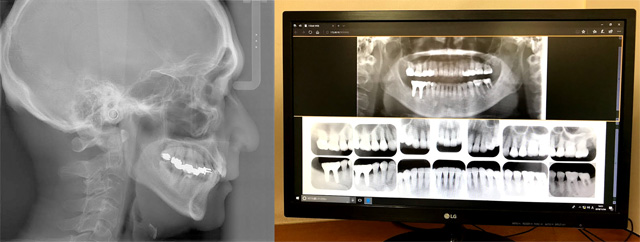

当院ではデジタルX線装置を使用しており放射線の被爆量は従来の10分の1程度です。撮影後すぐに目の前のモニターでレントゲンを見ることができます。